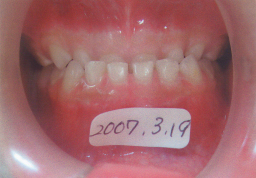

2008年01月29日(6才0ヶ月) 31番(左下切歯)の永久歯がはえてきました。 少し反対咬合 |